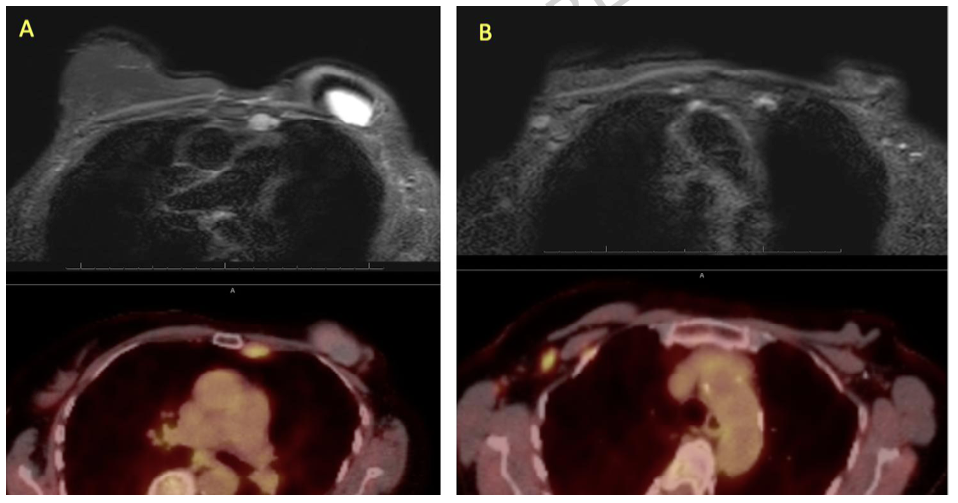

A) 非增强 MR 图像(上图)显示左侧内乳淋巴结内的硅胶信号,该淋巴结在 PET(下图)上呈 FDG 高摄取。

B) 非增强 MR 图像(上图)显示右侧腋窝淋巴结内的硅胶信号,该淋巴结在 PET(下图)上呈 FDG 高摄取。

为评估 MRI 检出的内乳淋巴结并排查远处转移,患者进行了 18F-FDG PET-CT 联合扫描。检查结果显示左侧内乳淋巴结代谢轻度增高 [标准摄取值 (SUV) 3.7,相对于肝脏平均 SUV 2.1],提示乳腺癌转移可能(图 1 和图 2)。

非增强硅胶假体专用MRI方案进一步证实左侧内乳淋巴结及右侧腋窝淋巴结内均存在硅胶(图4),并揭示左侧乳房假体存在包膜内及包膜外破裂。